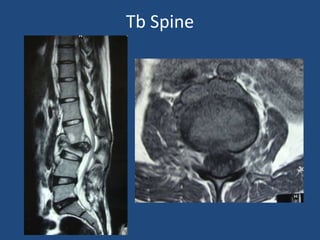

Tb Spine